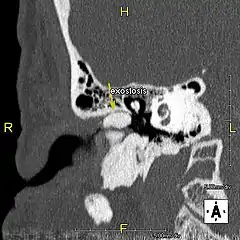

Conduit auditif avec exostose Conduit auditif avec exostose